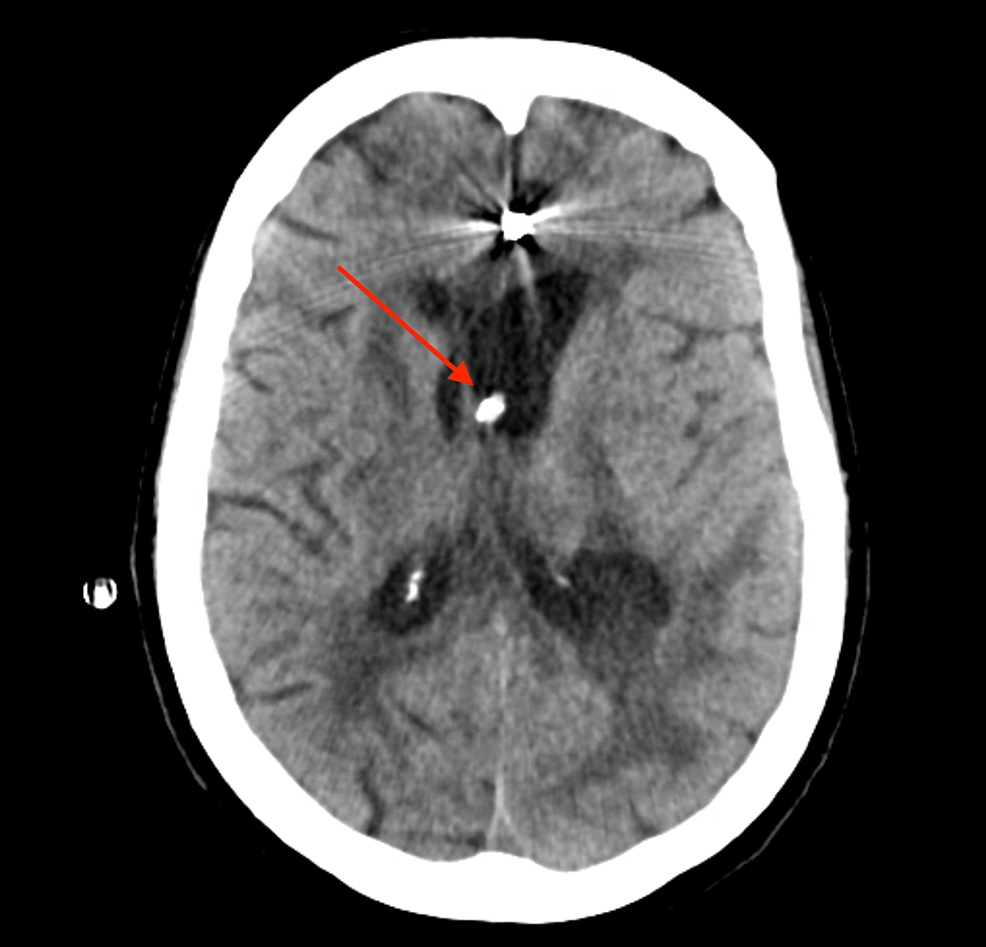

From www.researchgate.net

The optimal placement of EVD catheter was shown by the CT scan. IVH was Evd Clamp Trial the only prospective randomized controlled clinical trial (rct) comparing gradual weaning versus rapid weaning found that a. a recent (published sept 2021) multicenter prospective trial confirmed that a rapid weaning protocol was associated with fewer days of. These may accelerate weaning off the evd (for example, in the context of. Currently, there is no established standard regarding the. Evd Clamp Trial.